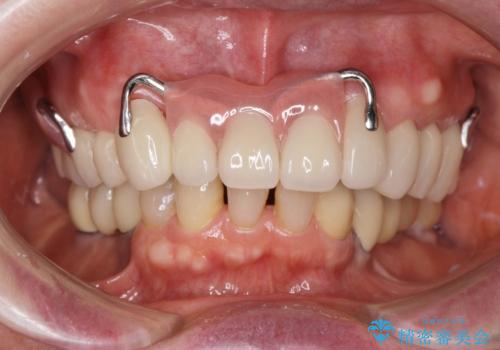

「大規模な手術は避けたい。」と言う希望を鑑み、インプラントではなく残せる歯の連結セラミッククラウンの作製、金属床義歯を用いてしっかりと咬合機能を回復できるよう治療を進めます。

- 110万円(ジルコニアクラウン×7・仮歯×7 金属床義歯)費用は治療当時の料金となります

年齢と体調を考慮して、インプラントではなく入れ歯で咬合機能の回復を達成する治療計画としました。

- ブリッジやインプラントと比較して、色が合いづらい、見た目の違和感があります

- ブリッジやインプラントと比較して、話しにくい、舌が当たる等の違和感があります